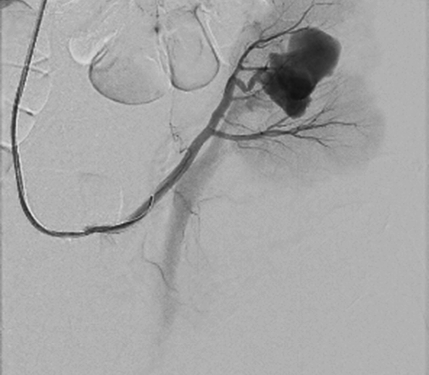

Right femoral artery was punctuated under local anesthetic. Inferior segmental artery was selectively cathe­terized and pseudoaneurysm was visualized. A microcatheter was inserted into segmental branch (Figure 4).

Figure 4. Renal pseudoaneurysm catheterized and visualized using contrast solution